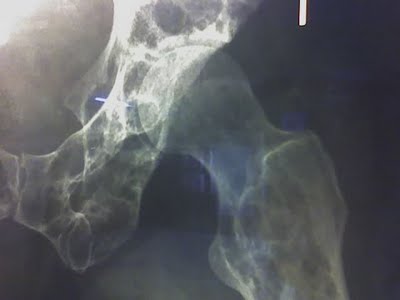

La enfermedad de Gorham-Stout (EGS) se define como una osteólisis masiva y espontánea caracterizada por la proliferación local de vasos pequeños linfáticos o vasculares resultando en una destrucción progresiva y resorción del hueso.

La EGS puede afectar uno o más huesos, a menudo contiguos, con sitios predominantes de afectación en la pelvis, la cintura escapulohumeral, la columna vertebral, costillas y cráneo. Durante la presentación, los signos clínicos incluyen dolor, hinchazón, y fracturas espontáneas. La osteólisis puede detener su progresión en cualquier momento, pero a menudo el tejido óseo desaparece completamente, dejando solamente una banda fibrosa residual, con un dramático desarrollo que inspira el término «la enfermedad de los huesos evanescentes o que desaparecen».